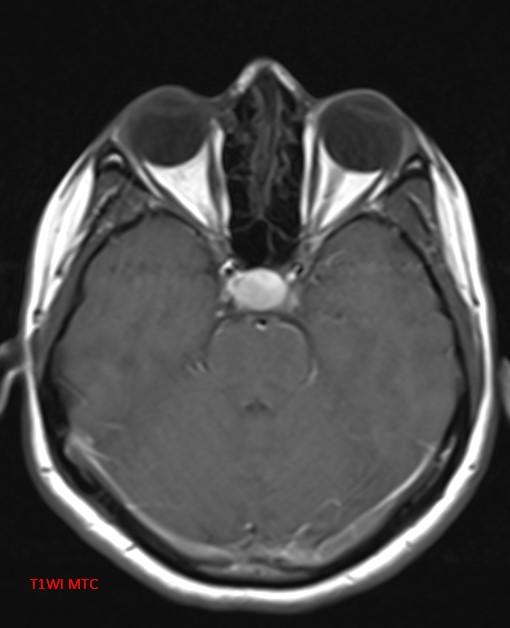

*30-year-old pregnant woman with headache and diplopia.

What is the most likely diagnosis?

Answer: Pituitary apoplexy

MR images reveal an ovoid lesion (red arrows) in the pituitary fossa with suprasellar extension. The optic chiasm is compressed (yellow arrows). The lesion is T1 and T2 hyperintense showing blood-blood fluid level (blue arrows).

• T1 C+: enhancement variable; usually peripheral.